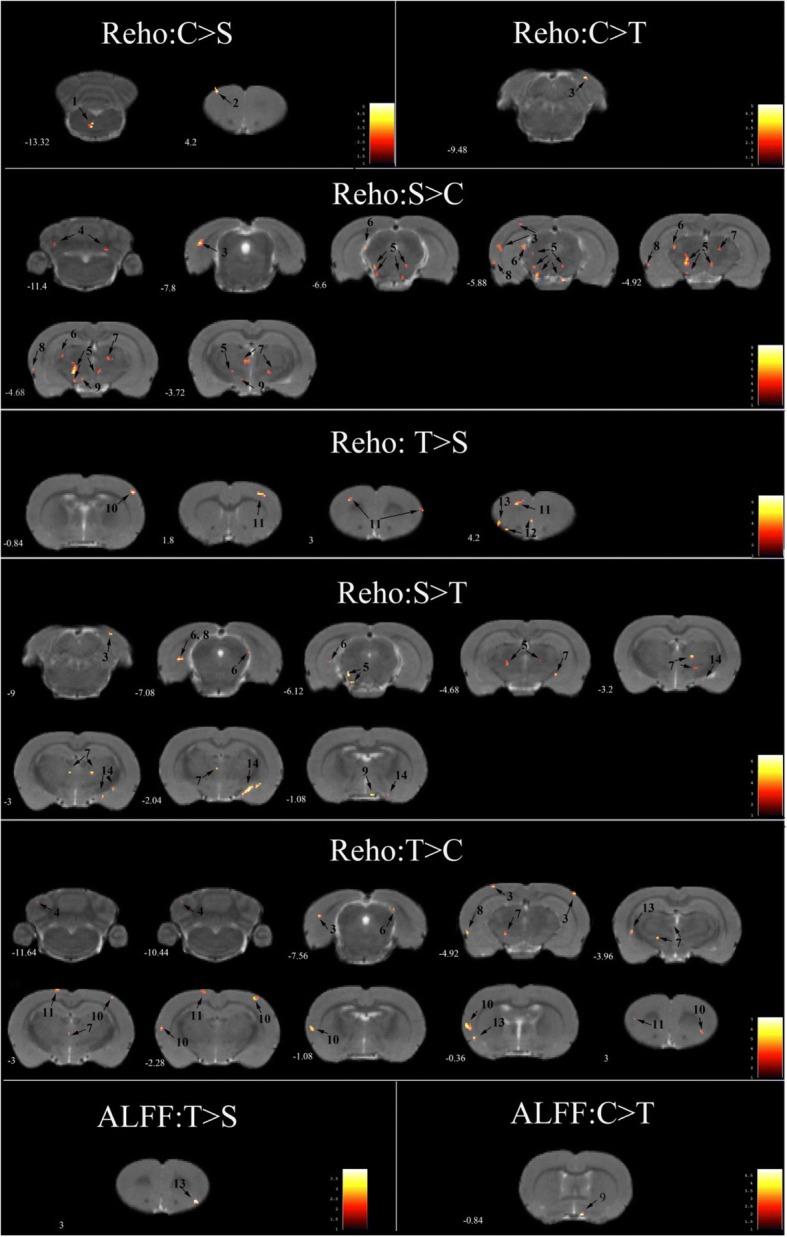

Thirty-two rats were divided into 4 groups: a control group(C group), a stress group(S group), a stress + telmisartan(0.5 mg/kg)group (T-0.5 mg/kg group) and a stress + telmisartan(1 mg/kg) group (T-1 mg/kg group). A behavioral battery, including an open field test (OFT), a sucrose preference test (SPT), and an object recognition test (ORT), as well as r-fMRI were conducted after 4 weeks of CUMS and telmisartan therapy. The r-fMRI data were analyzed using the amplitude of low-frequency fluctuations (ALFF) and regional homogeneity (ReHo) approach. The group differences in the behavior and r-fMRI test results as well as the correlations between these 2 approaches were examined.

RESULTS

CUMS reduced the number of rearings and the total moved distance in OFT, the sucrose preference in SPT, and novel object recognition ability in ORT. The telmisartan treatment (1 mg/kg) significantly improved B-A/B + A in the ORT and improved latency scores in the OFT and SPT. The S group exhibited a decreased ReHo in the motor cortex and pons, but increased ReHo in the thalamus, visual cortex, midbrain, cerebellum, hippocampus, hypothalamus, and olfactory cortex compared to the C group. Telmisartan (1 mg/kg)reversed or attenuated the stress-induced changes in the motor cortex, midbrain, thalamus, hippocampus, hypothalamus, visual cortex, and olfactory cortex. A negative correlation was found between OFT rearing and ReHo values in the thalamus. Two positive correlations were found between ORT B-A and the ReHo values in the olfactory cortexand pons.

32 只大鼠随机分为 4 组:对照组(C 组)、应激组(S 组)、应激+替米沙坦(0.5mg/kg)组(T-0.5mg/kg 组)和应激+替米沙坦(1mg/kg)组(T-1mg/kg 组)。经过 4 周 CUMS 和替米沙坦治疗后,进行行为学测试(旷场实验、糖水偏好实验、物体识别实验)和 r-fMRI 检查。r-fMRI 数据采用低频振幅(ALFF)和局部一致性(ReHo)分析方法进行分析。比较各组行为学和 r-fMRI 结果的差异,并分析两者之间的相关性。

结果

CUMS 降低了旷场实验中的后肢站立次数和总运动距离、糖水偏好实验中的糖水偏好率以及物体识别实验中的新物体识别能力。替米沙坦(1mg/kg)治疗显著提高了物体识别实验中的 B-A/B+A 比值,并改善了旷场实验和糖水偏好实验中的潜伏期评分。与 C 组相比,S 组运动皮质和脑桥的 ReHo 值降低,而丘脑、视皮质、中脑、小脑、海马、下丘脑和嗅皮质的 ReHo 值升高。替米沙坦(1mg/kg)治疗逆转或减轻了 CUMS 引起的运动皮质、中脑、丘脑、海马、下丘脑、视皮质和嗅皮质的变化。旷场实验中的后肢站立次数与丘脑的 ReHo 值呈负相关,物体识别实验中的 B-A 与嗅皮质和脑桥的 ReHo 值呈正相关。